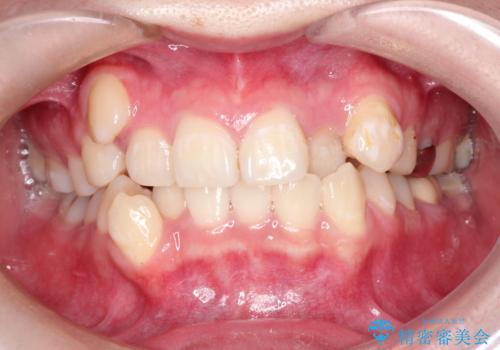

【モニター】犬歯のクロスバイトを目立たないワイヤー装置で